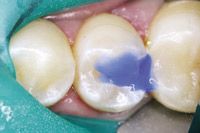

The following case demonstrates the use of TheraCal LC as a lining material:

The patient presents with a mandibular premolar with a large distal carious lesion (Figs. 1 and 2).

Fig. 1

Fig. 2

The caries were carefully excavated resulting in a deep preparation, especially on the axial wall (Fig. 3).

Fig. 3

A thin layer of TheraCal LC was placed on the dentin over the deepest portions of the preparation using the convenient syringe delivery system and then light cured for 20 seconds (Fig. 4).

Fig. 4